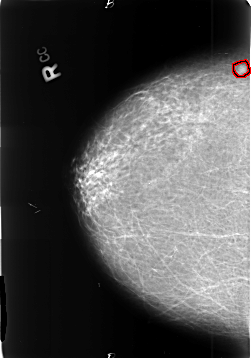

B_3402_1.RIGHT_CC

RIGHT_CC LINES 4648 PIXELS_PER_LINE 3256 BITS_PER_PIXEL 12 RESOLUTION 50 OVERLAY

FILE: B_3402_1.RIGHT_CC.OVERLAY

TOTAL_ABNORMALITIES 1

ABNORMALITY 1

LESION_TYPE MASS SHAPE OVAL MARGINS ILL_DEFINED

ASSESSMENT 4

SUBTLETY 3

PATHOLOGY MALIGNANT

TOTAL_OUTLINES 1

BOUNDARY